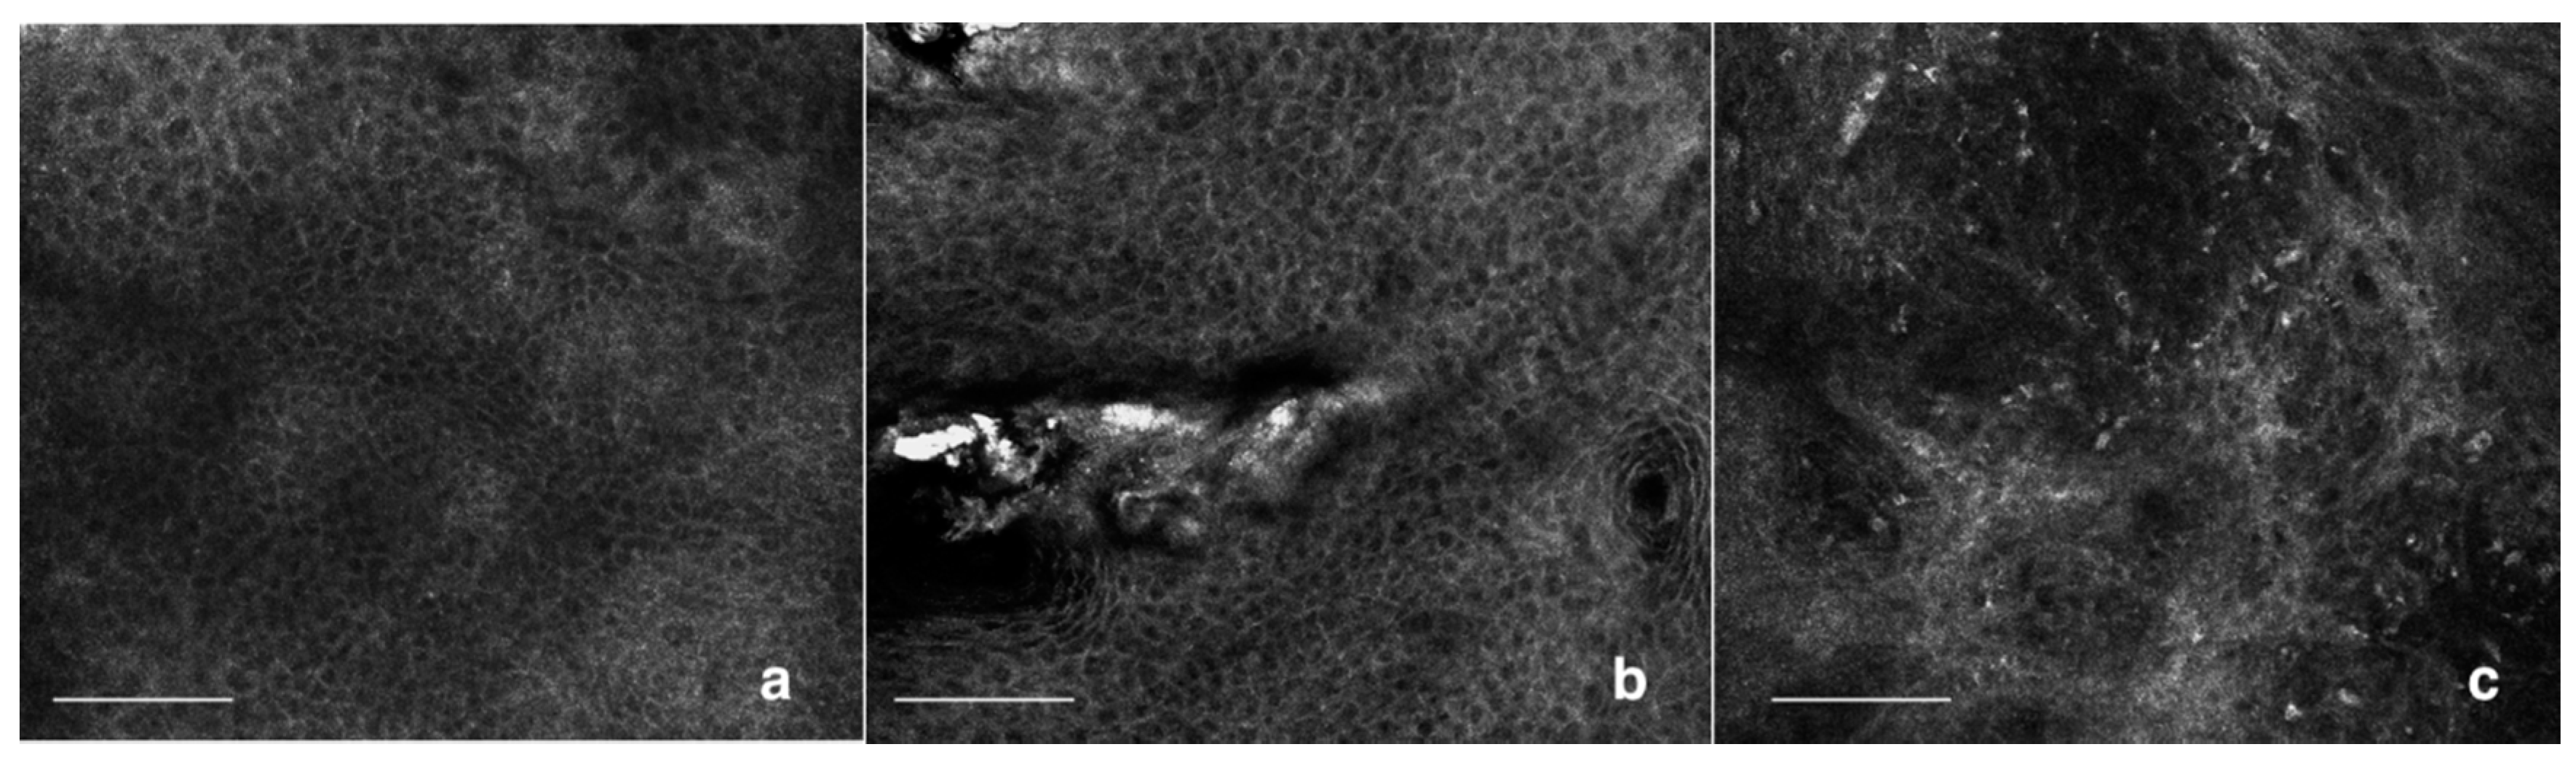

4. Fluorescence Techniques Detection in Skin Cancer

5. Confocal Aspects of AKs